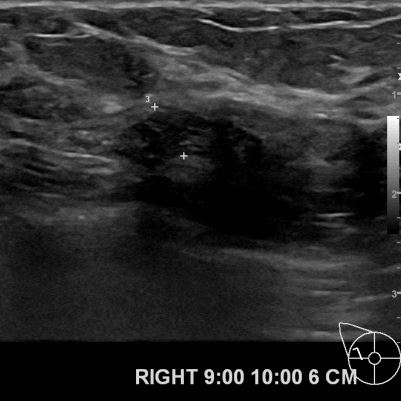

외부병원 초음파 검사상 조직검사권유로 내원하신 70대 여성분으로

우측유방 조직검사상 유방암으로 진단되었읍니다.